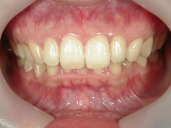

矯正歯科 治療前 正面

矯正歯科 治療後 正面